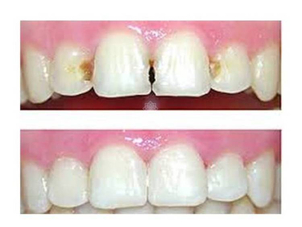

Antes y después, Clínica Dental Naran

En el caso de un tratamiento para una periodontitis leve, la recuperación será casi inmediata e indolora, notando las encías sanas a los 3 o 4 días luego de la limpieza profunda. En el caso de realizar un tratamiento regenerativo, la recuperación es más larga y lo más probable es que el periodoncista le recomiende seguir los siguientes pasos:

Antes y después. Foto de Clínica Dental Galápagos

Lo bueno de este tratamiento son los innumerables resultados que conlleva, ya que el paciente podrá percibirlos a los pocos días.

Entre los que más se destacan son: